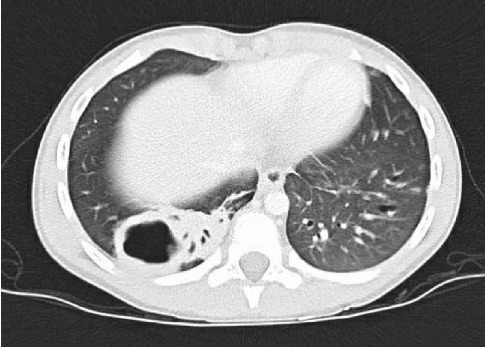

One week following the procedure, he was readmitted for recurrent fever and a new rounded lucency on chest X-ray in the right lung base, suspicious for cavitation or pneumatocele. Chest CT demonstrated a 2.5 × 3.2 × 3.7 cm area of cavitation within a region of consolidation or bronchiectasis in the posterior aspect of the right lower lobe with mediastinal and right hilar adenopathy, suspicious for cavitary bacterial pneumonia or fungal disease (Figure 8). Home treatment continued with the addition of intravenous ceftriaxone. Bronchoalveolar lavage culture from the previous week grew beta lactamase negative Haemophilus influenza and Moraxella catarrhalis. Fungal culture, mycobacterial culture, bronchial aspirate cell count, cytology, gastrin pepsin assay, and pathology report were all unremarkable. A PICC line was placed for 3 weeks of home antibiotics as a management for complicated cavitary pneumonia. Further workup included QuantiFERON-TB Gold, HIV assay, complement assay, tetanus antibody, diphtheria antibody, and pneumococcal antibody which were all unremarkable.

Figure 8.